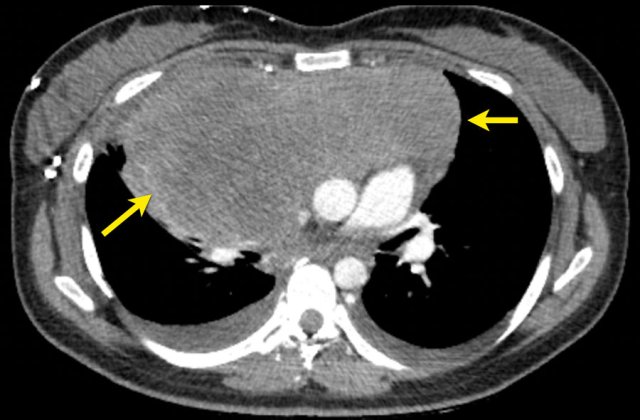

CT images in a 61-year-old male with melanoma during treatment.

At baseline the inguinal lymph nodes were to small to be used as target lesions and were regarded as non-target lesions.

At follow up there is unequivocal progression of the lymphogenic metastases.

CT images in a 61-year-old male with unequivocal progression of non-target lymphogenic metastases of melanoma during treatment. CT images in a 61-year-old male with unequivocal progression of non-target lymphogenic metastases of melanoma during treatment.